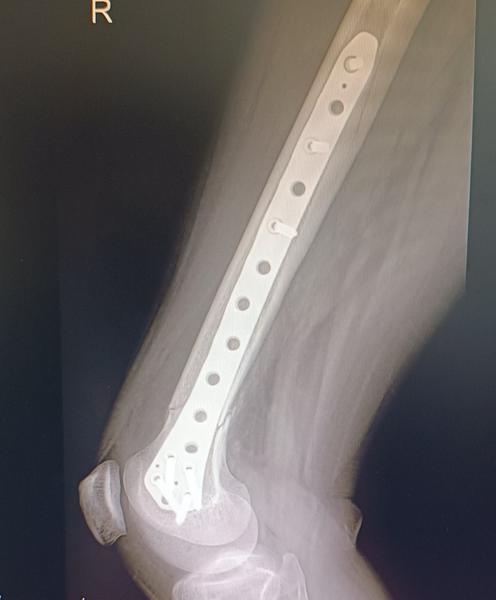

Dobrý deň ja mám platničku+ šroby v stehennej kosti ubehlo 14 mesiacov od operácie,mam naplánované vybraté teraz 30 apríla a som na prášky či do toho ísť alebo zrušiť 😞 názory lekarov niesu jednosmerné jeden bol za vybratie druhy načo ,primar na 60% ano na 40% nie mam 35 rokov dve male deti 2 r a 5r ešte som na rodičaku platnička mi nerobi nejake vyrazne problemy mam nohu len taku oťaženu v zime keď mrzlo ma pri dlho kracani bolelo koleno ale neviem či z platničky alebo zmena počasie 🥺 mam hrozný strach s tej operacie ta prva bola pre mňa trauma cele to čo sa mi stalo čo koľko bolestí som prežila a ty ľudia tam personal .. mám pocit že sa už zblaznim s toho každodenného rozmýšľania či to dať von alebo nechať plus mi na operáciu vychadza menštruácia takže cele zle poraďte ja viem že by som som sa skôr mala radiť s lekármi ale neviem už s akymi a skôr by som chcela počuť niekoho kto si tym vybratim prešiel 😢🙏